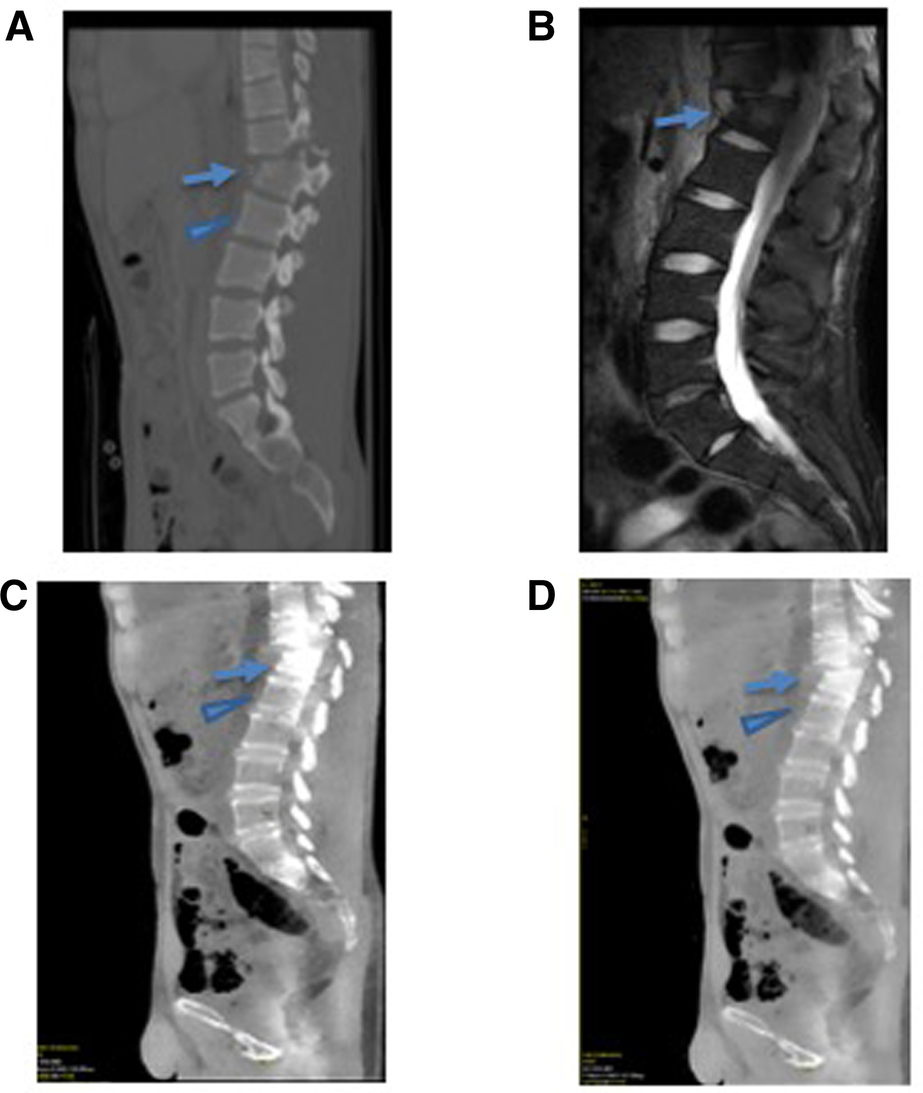

Figure 2

A 25-year-old male presenting with an acute thoracic spine fracture after a fall from a tree based on GSI dual-energy CT analysis with MRI correlate. (A) The conventional CT scan of the thoracic spine demonstrates a fractured T12 (arrow) and uninvolved L1 vertebral body (arrowhead). (B) The MRI STIR imaging demonstrates an increased signal within the fractured vertebral body (arrow) without a signal abnormality in the uninvolved adjacent L1 vertebral body (arrowhead). (C) Water (calcium) and (D) fat (calcium) images demonstrated a quantifiably increase in water content at the fractured T12 vertebral body (arrow) compared with the normal L1 vertebral body (arrowhead).

Elliptical ROIs were placed in the marrow cavity in regions of the fracture that demonstrated an increased STIR signal on the corresponding MRI. These ROIs were carefully placed avoiding the cortex, which was particularly challenging in the cervical vertebra, given the small size of the marrow cavity. For the normal, non-fractured control bone, a similar approach was utilized to avoid the corticated bone (Figures 2, 3).